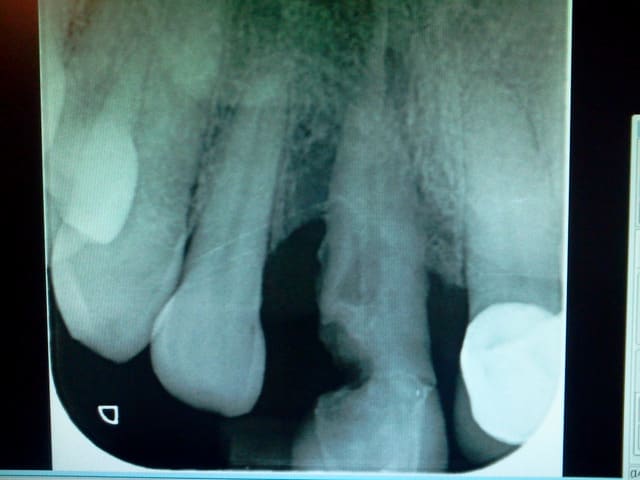

Une radio serait interessante.

Merci pour vos réponse j essaie de poster une rx demain.

Voilà la radio.

2013 03 26 20.14 - Eugenol